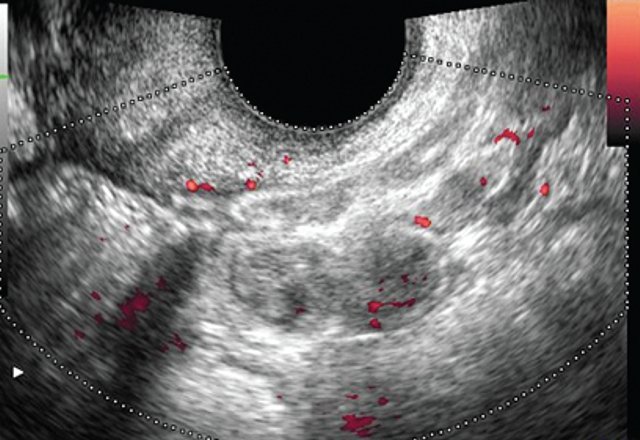

При УЗИ, проводимом по общепринятой методике полостным датчиком частотой 7 МГц, визуализировалась культя шейки матки с ровными четкими контурами размером 5,2х5,3х3,7 см. Структура ткани неоднородная, с наличием кист размером от 0,4х0,4 до 0,7х1 см. Цервикальный канал не расширен. Эндоцервикс не утолщен. Правый яичник расположен типично, его размер 3,5х1,9х3,5 см. Контуры четкие, ровные. В структуре определяются два аваскулярных жидкостных образования размером до 1 см с тонкими стенками и однородным содержимым. Левый яичник расположен типично, его размер 2,8х1,6х2,4 см. Контуры четкие, ровные. Структура умеренно неоднородная, фолликулы не определяются. Жидкости в позадиматочном пространстве не выявлено.

В полости малого таза, кзади от культи матки, определяется участок кишечника размером до 6,8х2,9х7,4 см с утолщенной до 0,5-0,6 см стенкой сниженной эхогенности. Перистальтика кишечника в данной проекции отсутствует, внутренний просвет дифференцируется нечетко. Содержимое кишечника практически не определяется, просвет сомкнут.